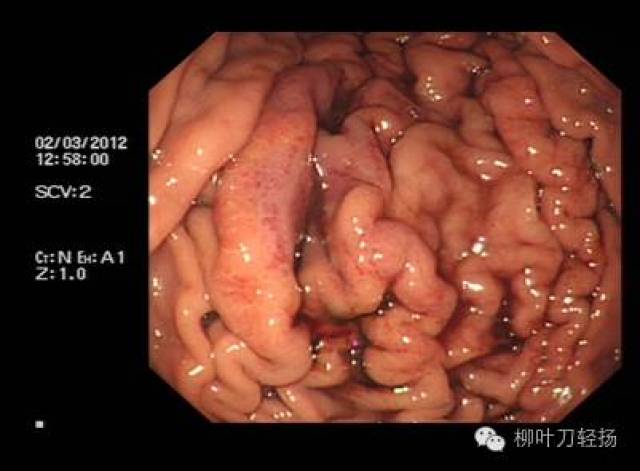

我国食管静脉曲张分级方法,按照食管静脉曲张形态及出血危险程度分为轻中重三级,具体如下1轻度曲张的静脉直径小于3mm,最初局限于食管下段,曲张呈直线形或略有迂曲无红色征2中度曲张的静脉直径在36mm,常累及食管的中段,管静脉曲张呈直线形,略有迂曲有红色征,或食管静脉曲张呈蛇形迂曲隆起但无红色征3;诊断方法内镜检查是确诊食管胃底静脉曲张的金标准,可直接观察曲张静脉的形态大小及范围,并评估出血风险影像学检查如腹部超声CT可辅助评估肝脏病变程度及门静脉高压状态,为治疗方案提供依据治疗原则治疗需个体化,依据病情严重程度肝功能状态选择方案药物治疗非选择性β受体阻滞剂如普萘。

头晕门静脉高压引发的食管静脉曲张可导致血压升高,患者可能出现头晕症状若病情严重,可能引发意识丧失甚至昏迷这种头晕与普通疲劳性头晕不同,需结合其他症状综合判断大便异常食管静脉曲张常由肝病或胃病引起,这些基础疾病本身可能导致大便异常患者可能发现粪便呈黑色或柏油色,这是消化道出血的典型;食管静脉曲张破裂出血是由于肝硬化失代偿期门脉高压导致的静脉曲张破裂所引起的消化道大出血以下是关于该病症的详细解释病因肝硬化失代偿期食管静脉曲张是肝硬化失代偿期的一种严重并发症门脉高压由于肝脏功能受损,门脉系统内的血液回流受阻,导致门脉压力升高,进而引发食管静脉曲张破裂机制;食管胃静脉曲张破裂出血是肝硬化门静脉高压最常见的并发症由于曲张的静脉管壁薄,且缺乏弹性收缩能力,一旦破裂,血液难以自行止住,出血量大且迅速,这会导致患者短时间内出现大量失血,进而引发休克等严重后果,所以该并发症的死亡率较高临床上对于食管胃底静脉曲张,尤其是已经出现破裂出血的情况;这导致静脉扩张,不能像正常情况那样收缩,形成曲张具体来说,静脉壁失去弹性,血液积累过多,使静脉直径超出正常范围,这就形成了所谓的食管静脉曲张这种病症并非仅限于食管,任何静脉回流受阻都可能导致此问题,但在门脉高压的病人中,食管静脉曲张尤其常见,且被视为严重并发症的一个标志;对于轻度食管静脉曲张,通常可以通过多种方法有效控制病情,减少出血风险药物治疗可降低门脉压力,预防静脉曲张破裂出血内镜下治疗可通过注射硬化剂或套扎等方式使曲张静脉闭塞手术治疗则通过切除部分胃或脾等降低门脉压力这些方法在早期干预中效果显著,多数患者可达到临床缓解但严重病例或合并其他。

它是肝硬化门脉高压的主要临床表现之一食管胃底静脉曲张的发生与肝脏病变密切相关,尤其是肝硬化并发症及危害食管胃底静脉曲张易引发血管破裂,导致大出血它是上消化道大出血的四大病因之一据文献统计,30%50%的患者在第一次大出血时可出现生命危险因此,食管胃底静脉曲张是一种严重的临床。